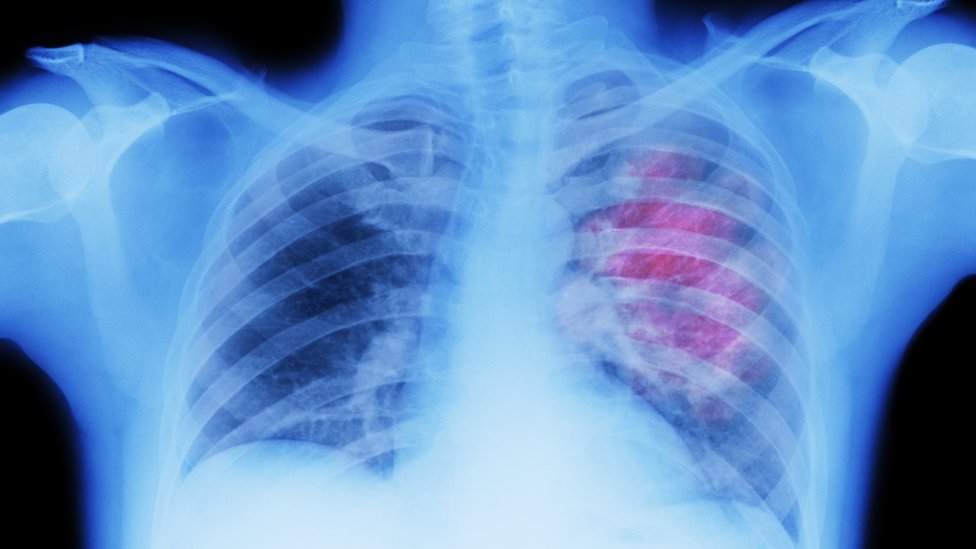

Los investigadores habían notado un vínculo entre una mejor supervivencia frente al cáncer de pulmón y una parte del sistema inmunológico, llamadas células B, que se agrupan alrededor de los tumores.

Qué estaban haciendo exactamente en el cáncer de pulmón era un misterio, pero una serie de intrincados experimentos con muestras de pacientes y pruebas con animales demostraron que todavía estaban intentando combatir virus.